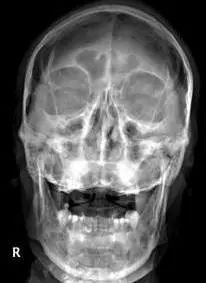

枢椎齿状突骨折前路空心螺钉固定术